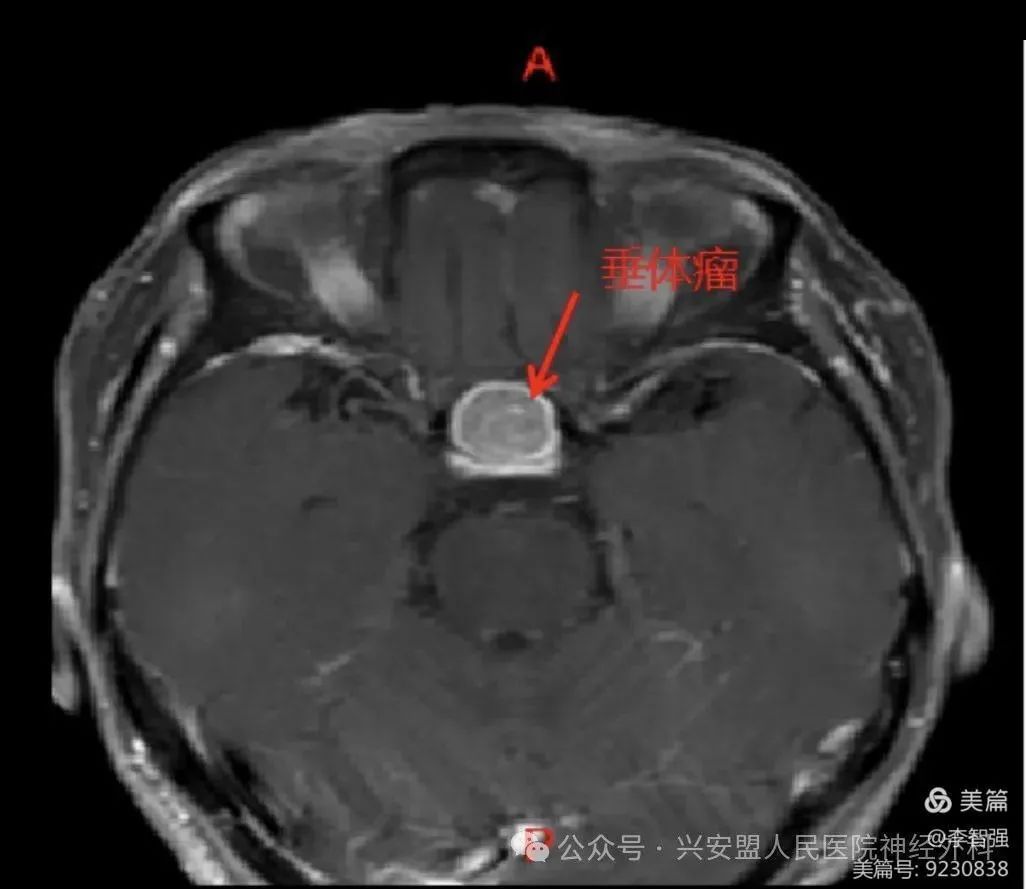

患者头颅核磁提示鞍区较大椭圆形病灶,视神经受压、上抬。

术前将头颅CT与核磁融合后,精准三维重建皮肤、颅骨、瘤体